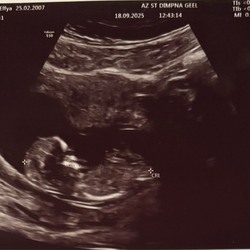

Ja was negatief net wel tetug licht getest meer of deze